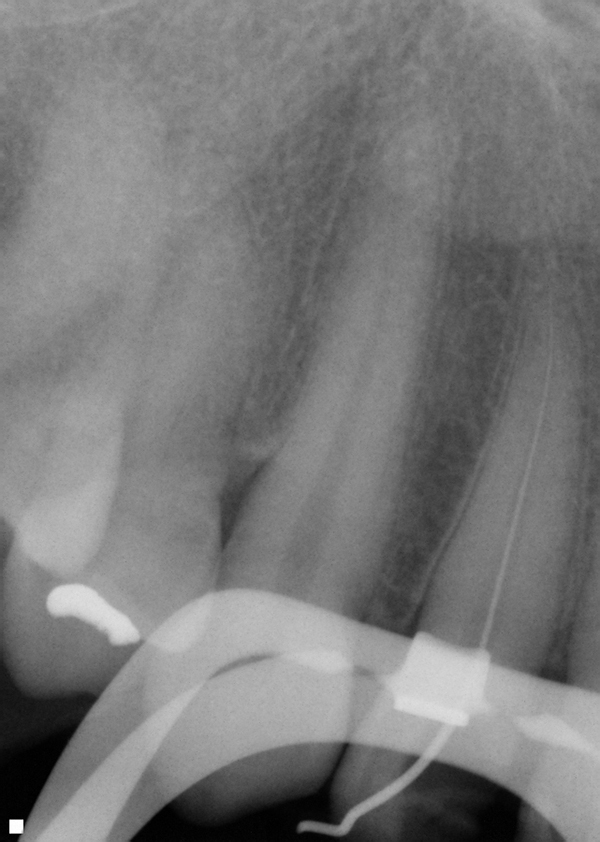

Preservation of tooth structure is critical for long-term survival of the tooth, especially in the cervical zone.1 When teeth are loaded under function, stress concentrates in the cervical area (Figure 1).2 Frequently, endodontically treated teeth require restoration with a crown or onlay due to the missing tooth structure related to decay or previous restorative materials (amalgam and composite). Decay must be removed, as well as previously placed restorative materials. However, the practitioner can attempt to preserve as much of the remaining tooth structure as possible; fundamental to this process is access for initiation of endodontics.

Fig 1. Stress concentration at the cervical of a molar under loading. (Image courtesy of Gene McCoy, DDS)

Figure 1

Fig 3. After decay and old restorative material removal to access the canal orifices, the tooth is potentially left in a weakened condition (left); after a pre-endodontic buildup to reinforce the remaining tooth while allowing access to the canals for endodontic treatment (right).

Figure 3